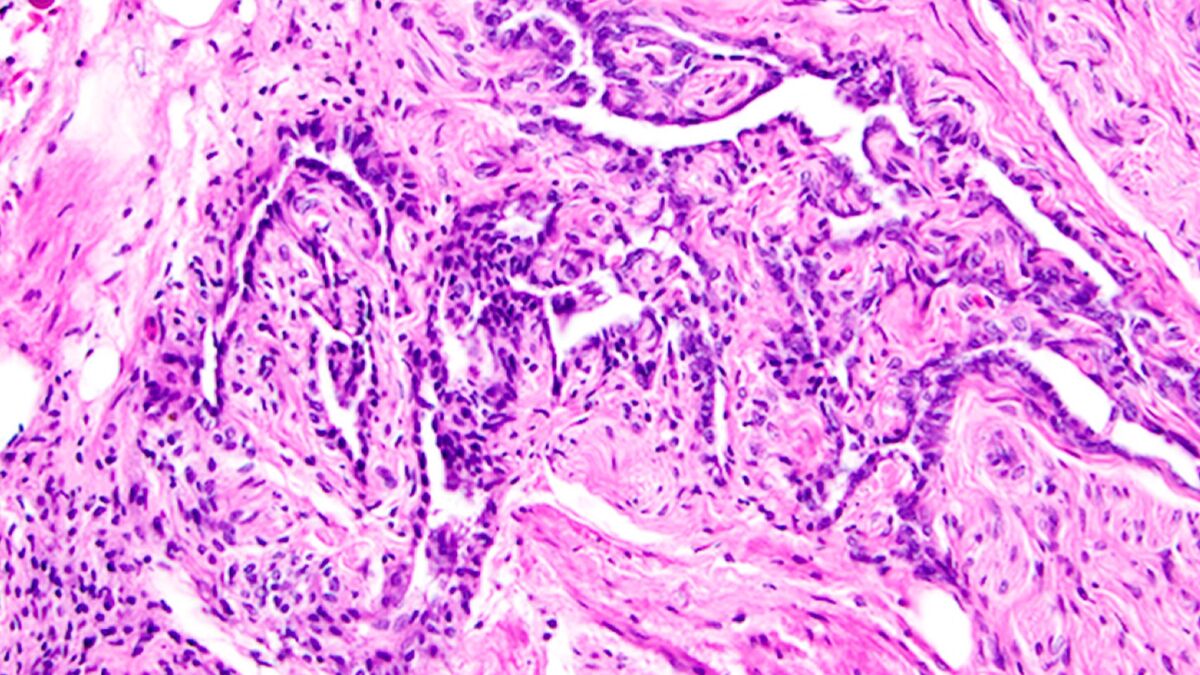

РО — подковообразная сеть трубок, расположенная под яичником, — была открыта у человека еще в 1870 году, но из-за отсутствия явных функций ее классифицировали как рудимент. Однако теперь, благодаря современным технологиям, ученые обнаружили, что эта структура активно взаимодействует с яичником, возможно, влияя на его развитие и гормональную регуляцию.

С помощью масс-спектрометрии исследователи обнаружили, что РО вырабатывает тысячи белков, включая IGFBP2 — фактор, связанный с ростом фолликулов в яичниках. Более того, эксперименты с флуоресцентным красителем показали, что жидкость внутри РО движется в сторону яичника, что указывает на возможную роль в его питании или сигнальной регуляции.